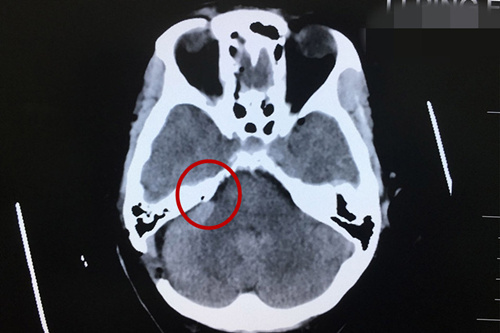

术后CT显示:小脑及脑干形态如常,未见明显异常密度病灶。